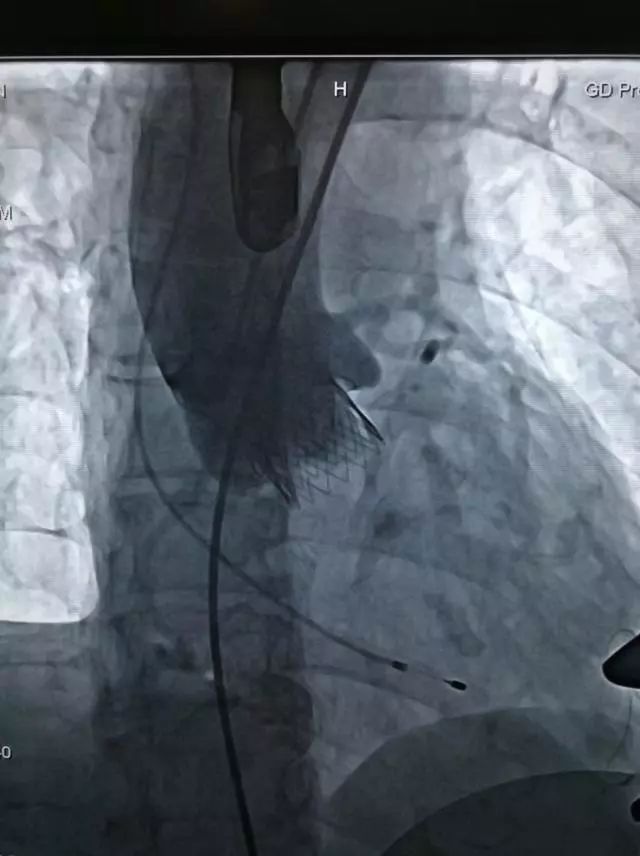

术中,在TAVI心脏手术团队的协作下,首先在患者心尖部位开一小孔,然后操控一根细长的输送鞘,将人工生物心脏瓣膜送入患者心腔。在造影屏幕监视下,新瓣膜被准确定位和放置于病变主动脉瓣位置。原来的心脏泵血“阀门”因关不紧“漏水”,新瓣膜“安装”完毕后,就像一扇运行良好的新“阀门”,一张一合地开始工作了。

人工瓣膜释放完成

整个手术过程非常顺利,仅耗1个半小时,胸骨肋骨无任何破坏,也无需体外循环,出血量未超过100ml。术后2小时老太太完全清醒过来并拔除气管插管,还能与医务人员轻松交谈。